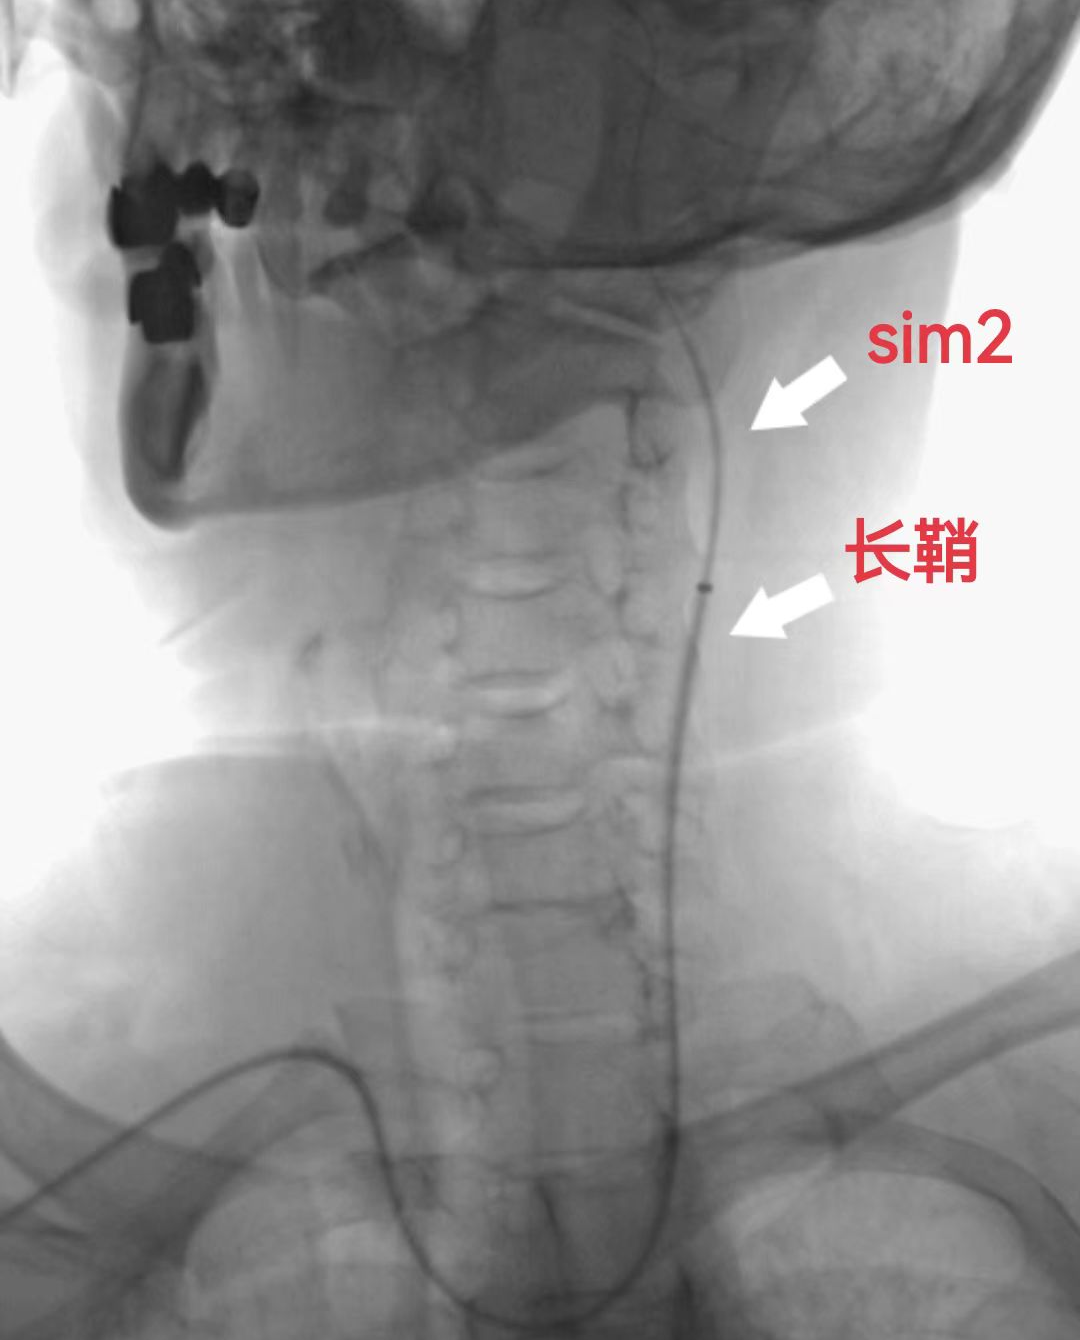

5F 125cm Sim2造影导管携5.5F Introsky X导管鞘成袢后超选左侧ICA。

什么叫桡鞘【例久弥新】寻道于桡——瑞康通5.5F Introsky X导管鞘经桡取栓一例_https://www.jmylbn.com_新闻资讯_第13张

什么叫桡鞘【例久弥新】寻道于桡——瑞康通5.5F Introsky X导管鞘经桡取栓一例_https://www.jmylbn.com_新闻资讯_第14张

泥鳅导丝、SIM2造影导管、5.5F Introsky X导管鞘同轴下继续跟进,尽可能高到位,随后引入V-18导丝。